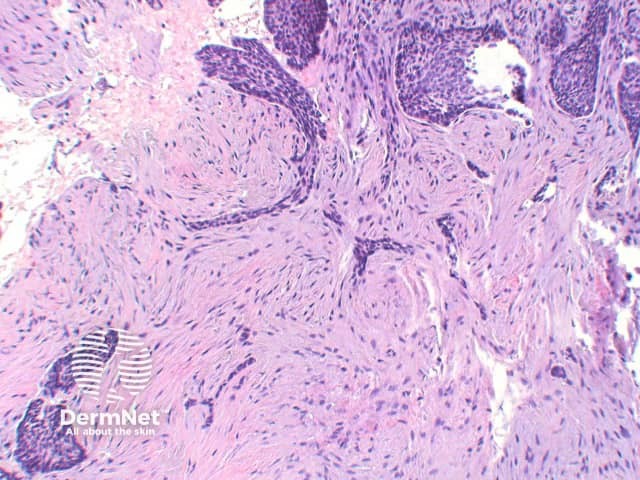

The key feature of basal cell carcinoma at low power magnification is of a basaloid epithelial tumour arising from the epidermis (figure 1). The basaloid epithelium typically forms a palisade with a cleft forming from the adjacent tumour stroma (figure 2). Centrally the nuclei become crowded with scattered mitotic figures and necrotic bodies evident (figure 3). A useful distinguishing feature from other basaloid cutaneous tumours is the presence of a mucinous stroma (figure 4). Some tumours may also show foci of regression, seen as areas of eosinophilic stroma with lack of basaloid nests.

Figure 4

Trichoepithelioma: The epithelium of trichoepithelioma demonstrates intimate integration with the surrounding matrix which is often cellular and fibromyxoid and show stroma. In contrast, basal cell carcinoma typically exhibits at least some retraction (clefting) between the epithelial cells and the surrounding epithelium and may show mucin deposition. Papillary mesenchymal bodies can serve as an important clue to trichoepithelioma. Immunohistochemistry is typically unhelpful but numerous stains are sited in the literature including Bcl-2, Ber-Ep4 and CD34. BCL2 staining is diffusely positive in basal cell carcinoma, while highlighting the basal layer of trichoepitheliomas. CD10, while positive in basal cell carcinomas and trichoepithelioma, tends to show peritumoral stromal reaction also.